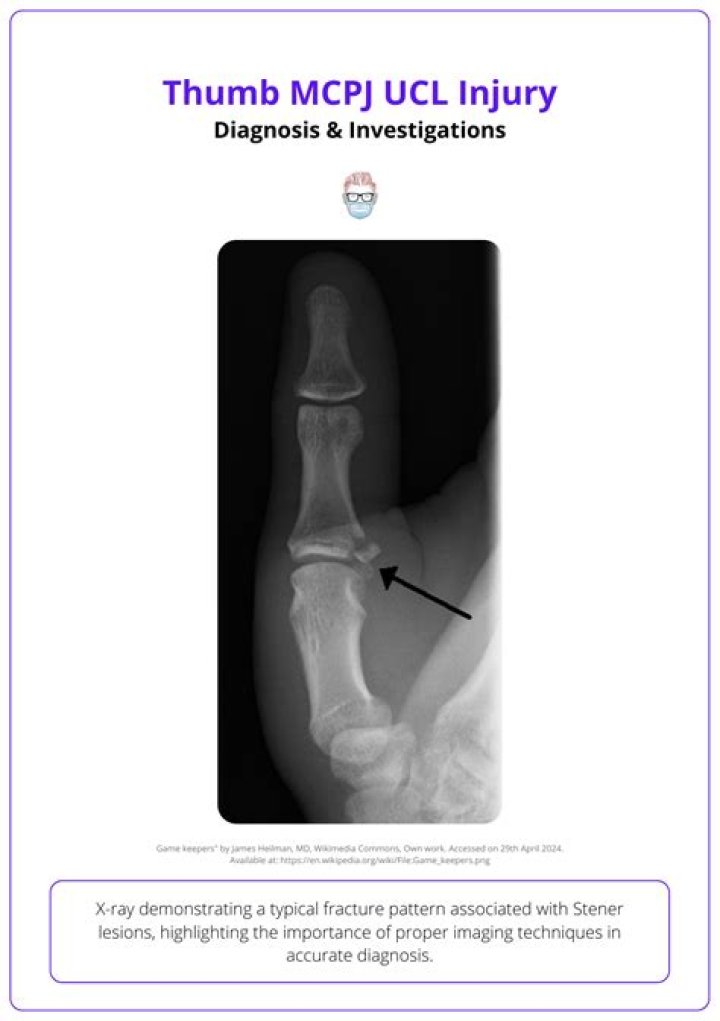

Metacarpophalangeal Joint (MP) The MP joint primarily allows you to bend and extend the thumb. The ulnar collateral ligament of the thumb MP joint is important to stabilize the thumb during most pinch activities and is commonly injured.

MCP collateral ligament sprain is most commonly an acute injury related to trauma. Mechanism of injury to the UCL of the MCP joint of the thumb is sudden, forced, radial deviation (abd…